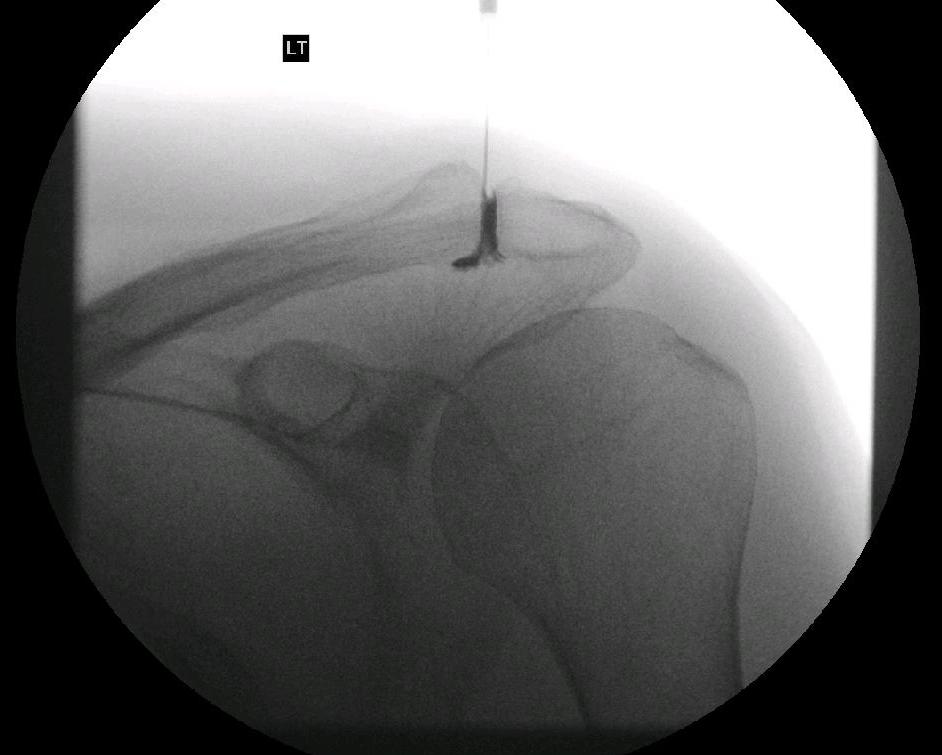

Depending on the problem the injection is targeted to the affected area. The subacromial space is easily injected. This is frequently done in an outpatient setting and rarely requires image guidance. The AC joint and the Glenohumeral joints are less reliably injected unless image guidance is used (typically x-ray or ultrasound)

When injecting into the Glenohumeral joint we use Omnipaque (Iohexol). This is an iodine based solution which shows up on x-ray allowing us to confirm we are in the correct place for injection.